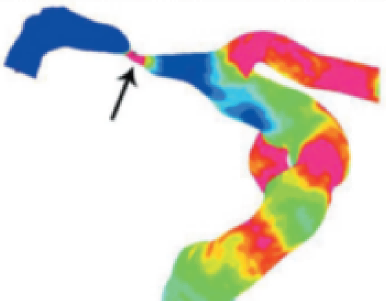

埃斯科核心实验室(IsCore image corelab) 是晓得(北京)商业发展有限公司旗下 的独立第三方核心实验室。由经验丰富的临床专家团队和影像放射专家团队组成, 致力于帮助临床医生和医疗领域的公司进行细致的、标准的、规范的影像管理和 判读。IsCore 影像实验室提供的影像判读数据已经为多家医疗机构的科研课题提 供数据支持,同时也已经协助国内外数个产品研发上市提供科学帮助。我们实验室的影像评价者均在国内顶尖专科医院接受过临床影像专业的系统学 习与规范培训,有多年的临床工作经验,以及强大的技术支持,能准确判读 MRI, HRMRI, DSA, OCT, CFD, VU 等影像,给出标准规范的报告结果,最低限度减少 了人为因素对试验结果的影响有助于科研成果产出和产品研发。